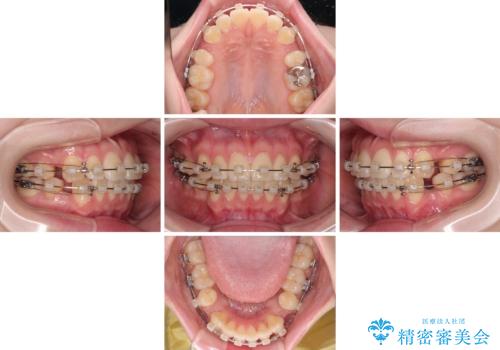

- 矯正装置

- クリアブラケット

- 治療期間

- 1年8ヶ月

舌の突出癖により、口元が突出しているだけでなく、上下前歯が非接触となっておりました。

舌のトレーニングをしっかりと行っていただくことで、2年を切って治療を終えるとともに

、上下前歯を接触させることができました。